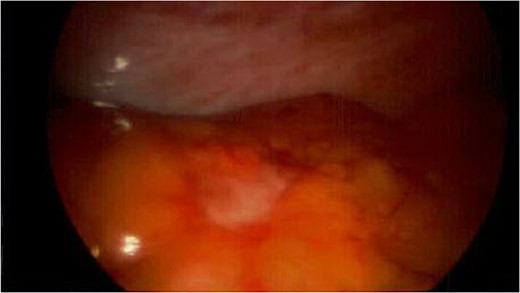

Spigelian hernia. Omental metastatic lesion protruding through the semilunar line.